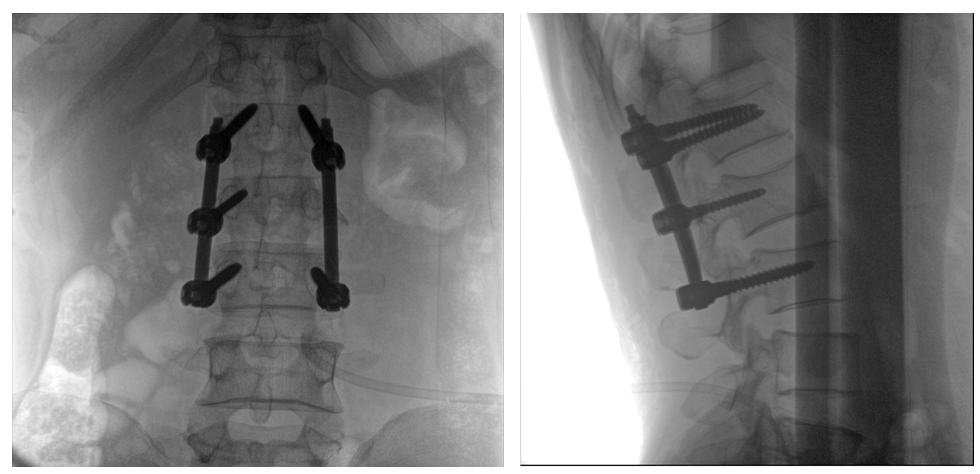

普爱医疗PLX119C大平板一体式C形臂采用30CM×30CM的平板探测器,在脊柱和长骨骨折等骨科手术治疗中,获取更大视野、更清晰的骨折部位图像,能够有助于医生在术中及时了解和评估骨折部位的对位、对线情况,且能进行长度和角度测量,为进一步提高手术质量提供强有力的支持。